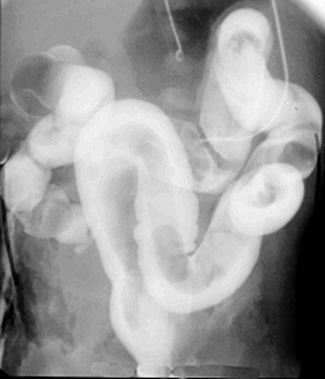

In meconium plug

syndrome, there is meconium obstruction of the colon, often seen in infants

of diabetic mothers or mothers who received magnesium sulfate for eclampsia.

Meconium forms a cast of the colon, and the colon remains normal in caliber.

| Meconium cast filling defect in colon on barium enema. |